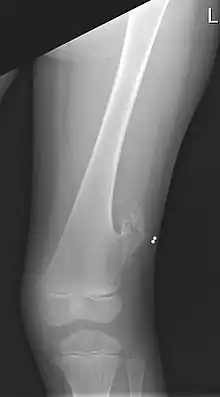

X-ray of the left femur of a 5-year-old boy with an exostosis at the lateral side, just above the knee. | |

An exostosis, also known as a bone spur, is the formation of new bone on the surface of a bone.[1] Exostoses can cause chronic pain ranging from mild to debilitatingly severe, depending on the shape, size, and location of the lesion. It is most commonly found in places like the ribs, where small bone growths form, but sometimes larger growths can grow on places like the ankles, knees, shoulders, elbows and hips. Very rarely are they on the skull.